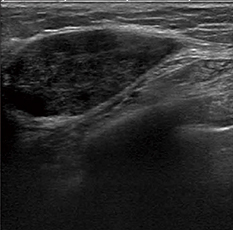

●Strain elastography

プローブの圧迫動作により,病変部位の硬さ(弾性)を映像化します(図3)。プローブの動きをグラフ化することで,圧迫の与え方が適切であるかどうか確認できます。さらに,再現性の高い弾性イメージング検査が可能となりました。

図3 Strain elastography |

| (画像ご提供:名古屋医療センター・遠藤登喜子先生) |